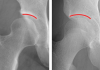

[Á¦ÁÖ, Á¦ÁÖÀÎÀÇ °Ç°º¸°í¼ ¥· °Ç°´ÙÀ̾] (143)´ëÅðºñ±¸ Ãæµ¹ÁõÈıº(FAI)

»À³¢¸® ºÎµúÃÄ °üÀý ¼Õ»ó À¯¹ß½Åü¡¤¿µ»ó µî Á¤È®ÇÑ Áø´Ü Çʼö½ºÆ®·¹Äª¡¤Àú°µµ ¿îµ¿ µî µµ¿ò [ÇѶóÀϺ¸] Çö´ë¡¦